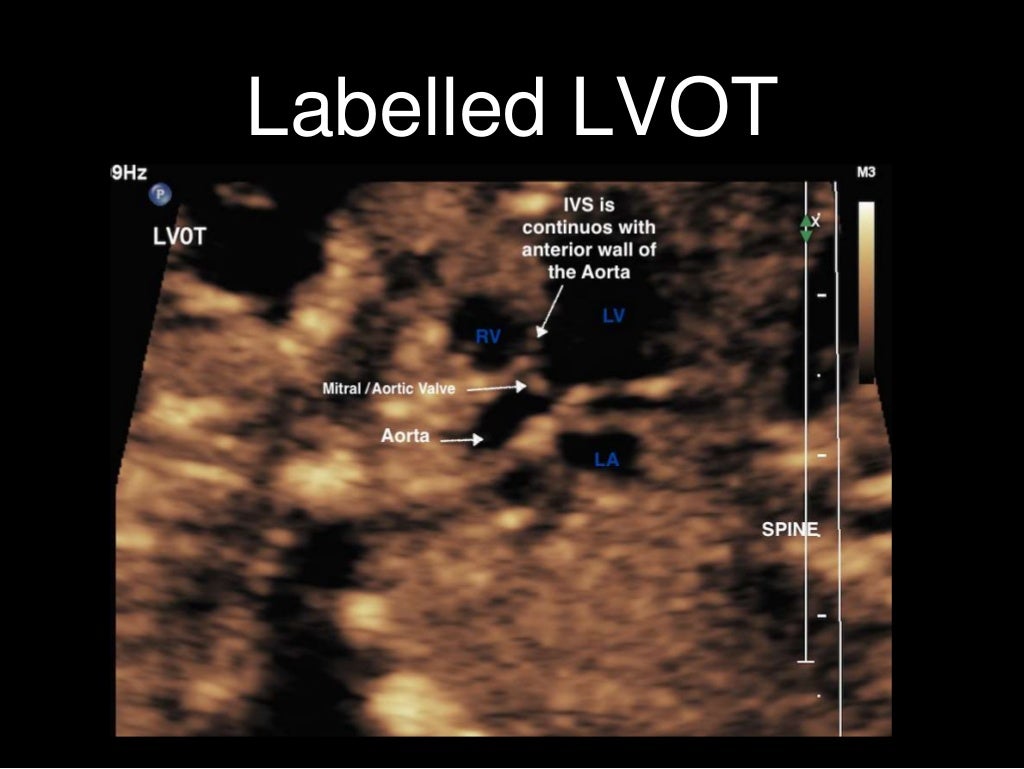

Labelled fetal heart ultrasound Heart Block Fetal Ultrasound Ultrasonography has shown that intrauterine diagnosis of abnormal fetal rhythm is common nowadays. It is rare for a fetus with hydrops, complete heart block and structural heart disease to survive (1,2). Fetuses with complete heart block and structurally normal hearts are. Congenital heart block is a rare finding, occurring in approximately 1 : Experts recommend patients at risk to have. Heart Block Fetal Ultrasound.